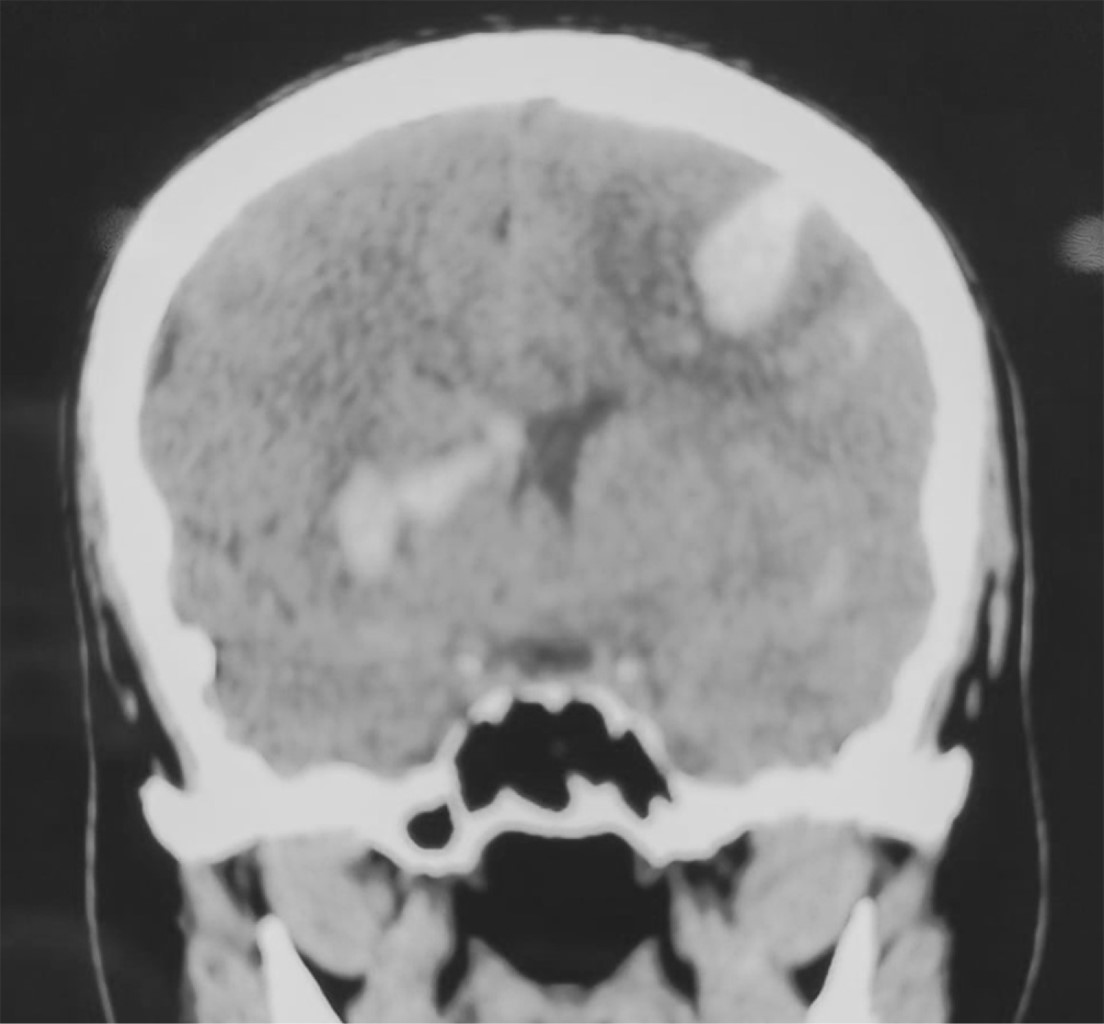

Introduction: primary vasculitis of the central nervous system (PVCNS) is rare, with heterogeneous clinical presentation. Case report: 35-years-old female with seven days with headache, without improvement with analgesics, adding vomiting and stupor, right hemiparesis, and aphasia; CT showed hemorrhages in the right caudate nucleus and left frontal lobe, laboratory tests including antibodies and acute phase reactants normal; pan-angiography showed: a pattern of vasculitis of trunk branches in cerebral arteries and occlusion of the inferior longitudinal sinus; with a diagnosis of possible PVCNS. Drainage of frontal hemorrhage and biopsy was performed, which confirmed the diagnosis; beginning treatment with methylprednisolone bolus and cyclophosphamide, obtaining clinical improvement. Conclusions: PVCNS presents heterogeneous clinical manifestations of acquired neurological deficits; it is a challenge. Its diagnosis implies the existence of the following: a) the acquired neurological deficit, unexplained by another cause, b) angiographic or histopathological evidence of PVCNS, c) absence of systemic vasculitis or other condition that explains it.

Figure 4